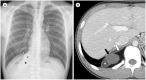

The mediastinum is the most prevalent site of extragonadal teratomas. Patients with mediastinal mature teratomas are usually young adults, and the condition does not show significant sexual differences. Mediastinal teratomas are mostly located in the anterior mediastinum. Patients are usually asymptomatic, although they can have several complications when the teratomas become large or rupture. Most mediastinal teratomas can be diagnosed using CT. Diagnosing ruptured or malignant teratomas is challenging because of their atypical clinical and radiological presentations. In this article, we describe various manifestations of mediastinal teratomas, with an emphasis on radiologic features.